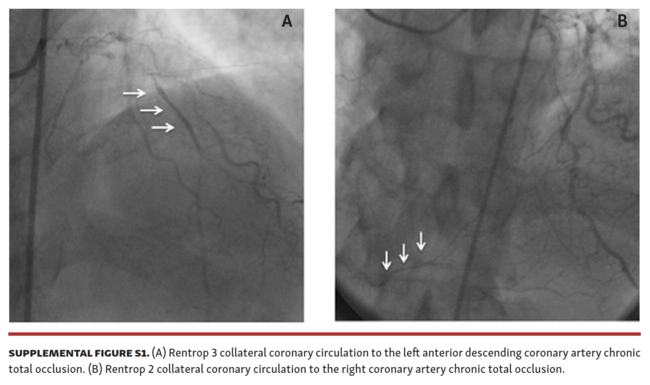

Angiographic assessment of collaterals. Views with the least foreshortening of the collateral connection were selected for the angiographic diagnostic analysis at a centralized core laboratory. Collateral filling of the recipient artery was evaluated according to the Rentrop classification, which consists of 4 classes: 0 = no filling of any collateral; 1 = filling of sidebranches of the epicardial artery; 2 = partial filling of the epicardial vessel; and 3 = complete filling of recipient artery by collaterals.10 For the purpose of this report, we divided our population into two groups; those with Rentrop grade 3 (group 1) and those with Rentrop 1 or 2 (group 2).

Baseline characteristics. During a 1-year period, 80 patients were screened, and 20 met the criteria for this study (Figure 1), Study participants were divided based on Rentrop grade, a method to rate the collateral filling of the recipient artery (Supplemental Figure S1). Those with Rentrop grade 3 (n = 7) comprised group 1 and all others (n = 13) comprised group 2 (7 participants [53.8%] with Rentrop grade 2 and 6 patients [46.2%] with Rentrop grade 1). Table 1 shows the baseline clinical characteristics. The 2 groups did not differ in any way except in major triglyceride levels, where the median was 2.2 mmol/L (IQR, 1.8-2.3 mmol/L) in group 1 vs 1.0 mmol/L (IQR, 0.5-1.6 mmol/L) for group 2 (P=.01). Although not statistically significant, group 1 had a higher proportion of participants with severe clinical angina or silent ischemia compared with group 2. The medical therapies also did not differ between the 2 groups except that group 2 had a higher proportion of participants treated with oral nitrates (46.2% in group 2 vs 0.0% in group 1; P=.05).